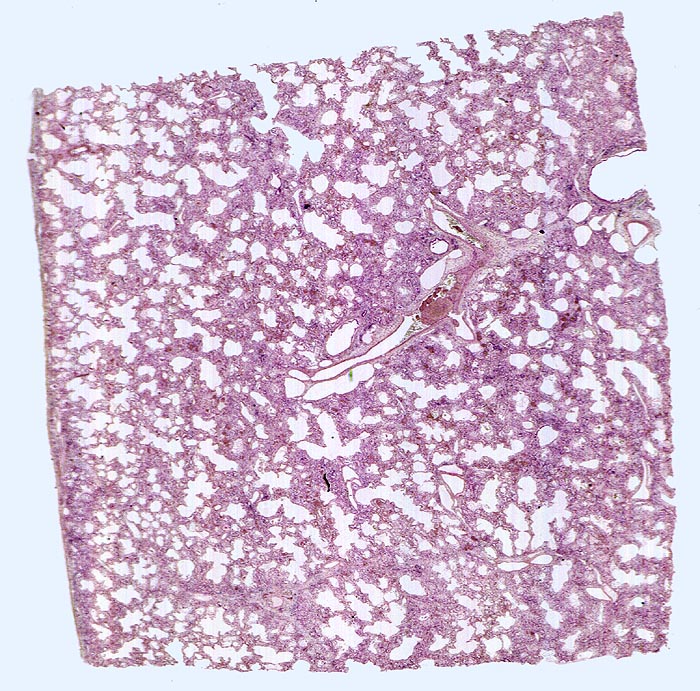

PathoPic – image database / PathoPic ID 4689 - Diffuser Alveolarschaden, exsudatives und proliferatives Stadium

Diffuser Alveolarschaden, exsudatives und proliferatives Stadium

In der Übersicht ist eine diffuse Verbreiterung der Alveolarsepten erkennbar.

Der diffuse Alveolarschaden ist das morphologische Korrelat des ARDS (klinischer Begriff).